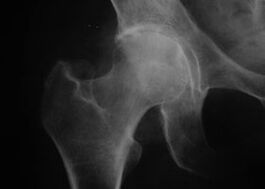

Appearance of joint with arthrosis

Coxshrosis, arthrosis of the hip joint

A classic clinical picture of arthrosis is observed with this disease.

The first symptom of coxarthrosis is discomfort in the hip joint after physical activity.

With progressive coxarthrosis, pain increases, stiffness and limited mobility appear.

Patients with a severe form of coxarthrosis should refrain from stepping on the affected extremity and choose positions where the pain is least noticeable when stationary.